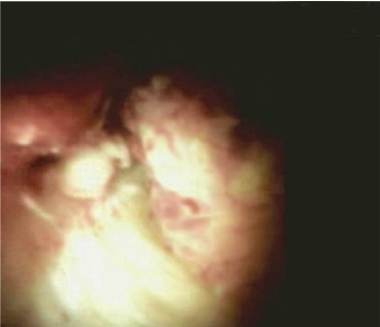

При выполнении холангиоскопии при визуальной оценке слизистой желчных протоков на уровне средней трети определяются гиперемия и полнокровие подслизистых сосудов, отечность тканей с формированием сужения до 2 мм, непроходимого для холедохоскопа. При этом явного экзофитного образования не определяется. Под визуальным контролем выполнена множественная биопсия тканей.

Данные морфологического исследования – в полученном материале найденные изменения крайне похожи на код: 8140/3 Аденокарцинома.

Заключительный диагноз: опухоль Клацкина T4N1M0 IV A ст., Бисмут IV.

Рис. 4б. Изображение транспапиллярной холангиоскопии с помощью системы SpyGlass.

Fig. 4b. SpyGlass image.